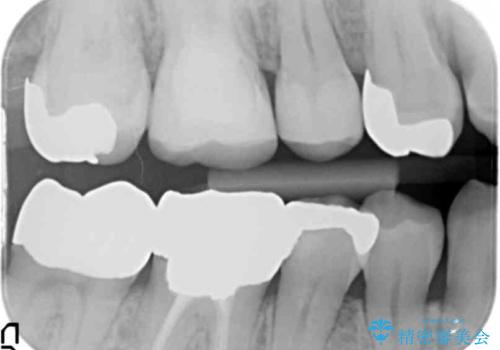

- 右下奥の銀歯の下が虫歯になっていました。

歯ぐきの下までしっかり修復するために、歯周外科手術を含めた治療を行いました。

今回は、歯周外科手術を行い、歯ぐきの厚みを薄くし、また、歯槽骨の高さも整えて、歯周環境を整えました。

そうすることで、正確に歯型もとれ、精密なクラウンが製作でき、再度虫歯になる可能性を低くできます。